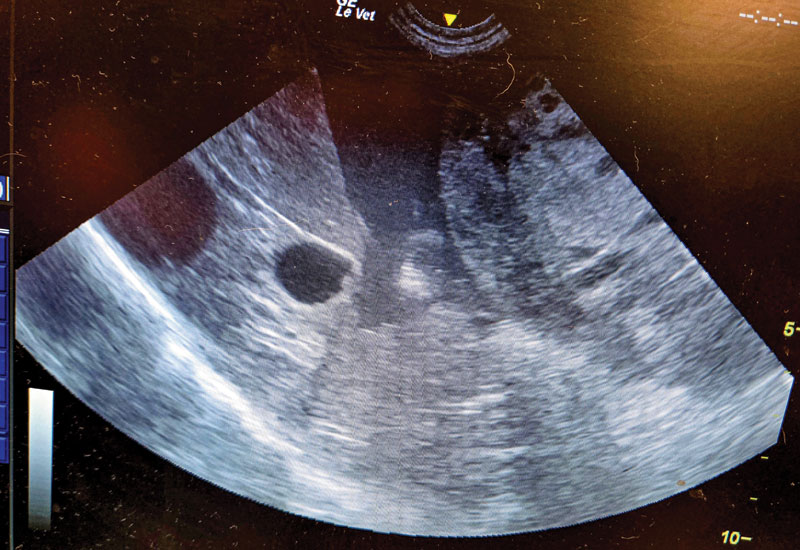

4) Figure 4. An example of significant peritoneal fluid showing an abnormal liver and spleen (or just a mass that used to be the spleen). This patient has a similar presentation to the patient in Figure 3.

Peritoneal effusion, abnormal spleen and liver, confirmed hemoabdomen.